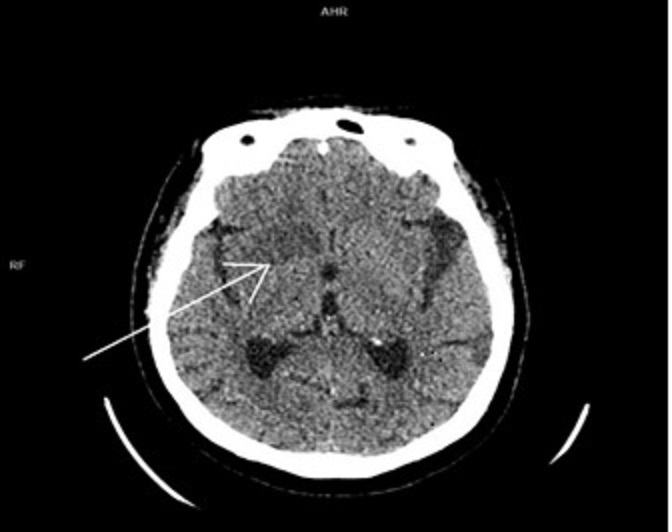

Геморрагические осложнения выявлены после лечения у 42 (9,1%) пациентов: у 23 (8,7%) пациентов 1 группы, 10 (11,5%) человек 2 группы и 9 (9,9%) пациентов 3 группы. В исследовании учитывали внутричерепные кровоизлияния, выявленные при МСКТ, которые были симптомные с ухудшением неврологического дефицита не менее 4 баллов по NIHSS. Установлено, что частота ГТ была существенно выше при большом размере очага (рис. 1): среди пациентов с очагом ишемии более 2 см — 70,3%, при очаге менее 2 см — 13,5% (p=0,001).

Рисунок 1 - Пациент Н., 70 лет, с острым ишемическим инсультом до эндоваскулярной тромбэкстракции, осложнившейся геморрагическим пропитываем очага ишемии

Примечание: мультиспиральная компьютерная томография головного мозга без контрастного усиления в аксиальной проекции: зона снижения денситометрической плотности в правой лобной доле (+22 HU) размерами 29 х 19 мм (стрелка) – ASPECTS 8 (бассейн правой СМА)